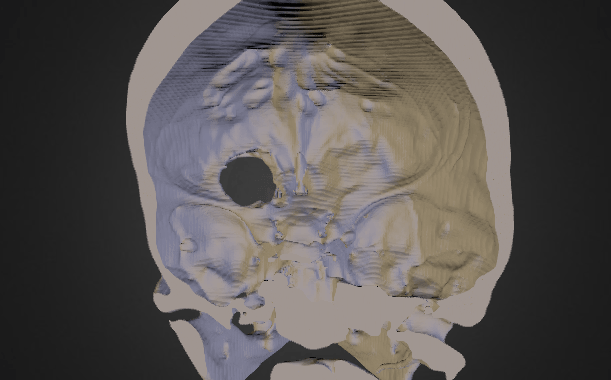

In the meantime, Balzer, a 3D-printing enthusiast and former software engineer for the Air Force, used Scott’s imaging files and a Photoshop mockup to monitor the tumor’s development. Then he decided to really put his expertise to use:

I thought, ‘why don’t we take it to the next level? Let’s see what kind of tools are available so that I can take the DICOMs (digital format for medical imaging data), which are 2D slices, and convert them into a 3D model.

Balzer (who explained in a MakeZine comment section that “Pamela did all the research on the medical end, she is the person to have at your side when things go south. Think of me as her IT department”) created a 3D rendering of his wife’s cranium with a representation of the tumor, then put the images up on Sketchfab. There, the model was seen by a neurosurgeon who recommended a minimally invasive surgery that would extract the growth via Scott’s eyelid (to assist with the procedure, Balzer even sent the doctor a life-sized 3D model of his wife’s skull).

By the time Scott’s tumor was successfully removed last year, it was close to causing permanent damage to her optic nerves. Had she waited even six more months, her vision might have been irreparably damaged.

(via Daily Dot, image via Sketchfab)